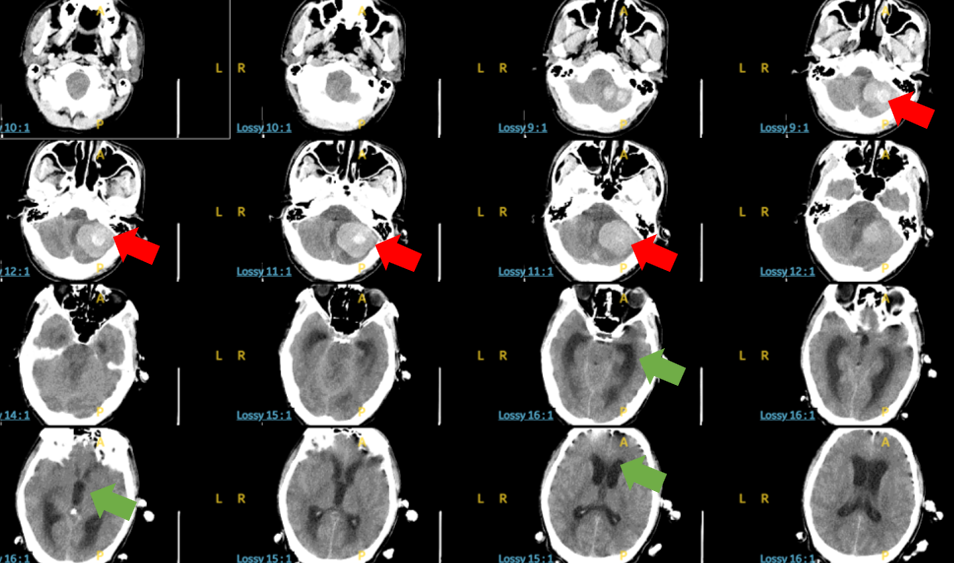

到院时,患者已陷入昏迷,无法言语,呼吸急促,躁动不安并伴有大量呕吐。急诊科团队立即启动绿色通道,紧急完成头颅CT及脑血管检查,结果提示脑出血(脑内血肿),并已引发急性脑积水、枕骨大孔疝——这意味着脑组织正遭受严重压迫,脑干功能濒临衰竭,患者随时可能出现呼吸、心跳骤停,生命危在旦夕。

术前头颅CT:红色箭头示巨大脑内血肿,

绿色箭头是脑积水导致幕上脑室系统扩张,脑组织受压

手术在当晚迅速开展。在麻醉科的精准护航下,张培海主刀,手术顺利实施,术中可见,原本因高压而高度膨胀的脑组织逐渐恢复常态。术后复查头颅CT显示脑内血肿病灶已清除,脑积水明显缓解。从患者晚9点多被送至急诊至次日凌晨4点手术完成,仅共用时6小时左右。